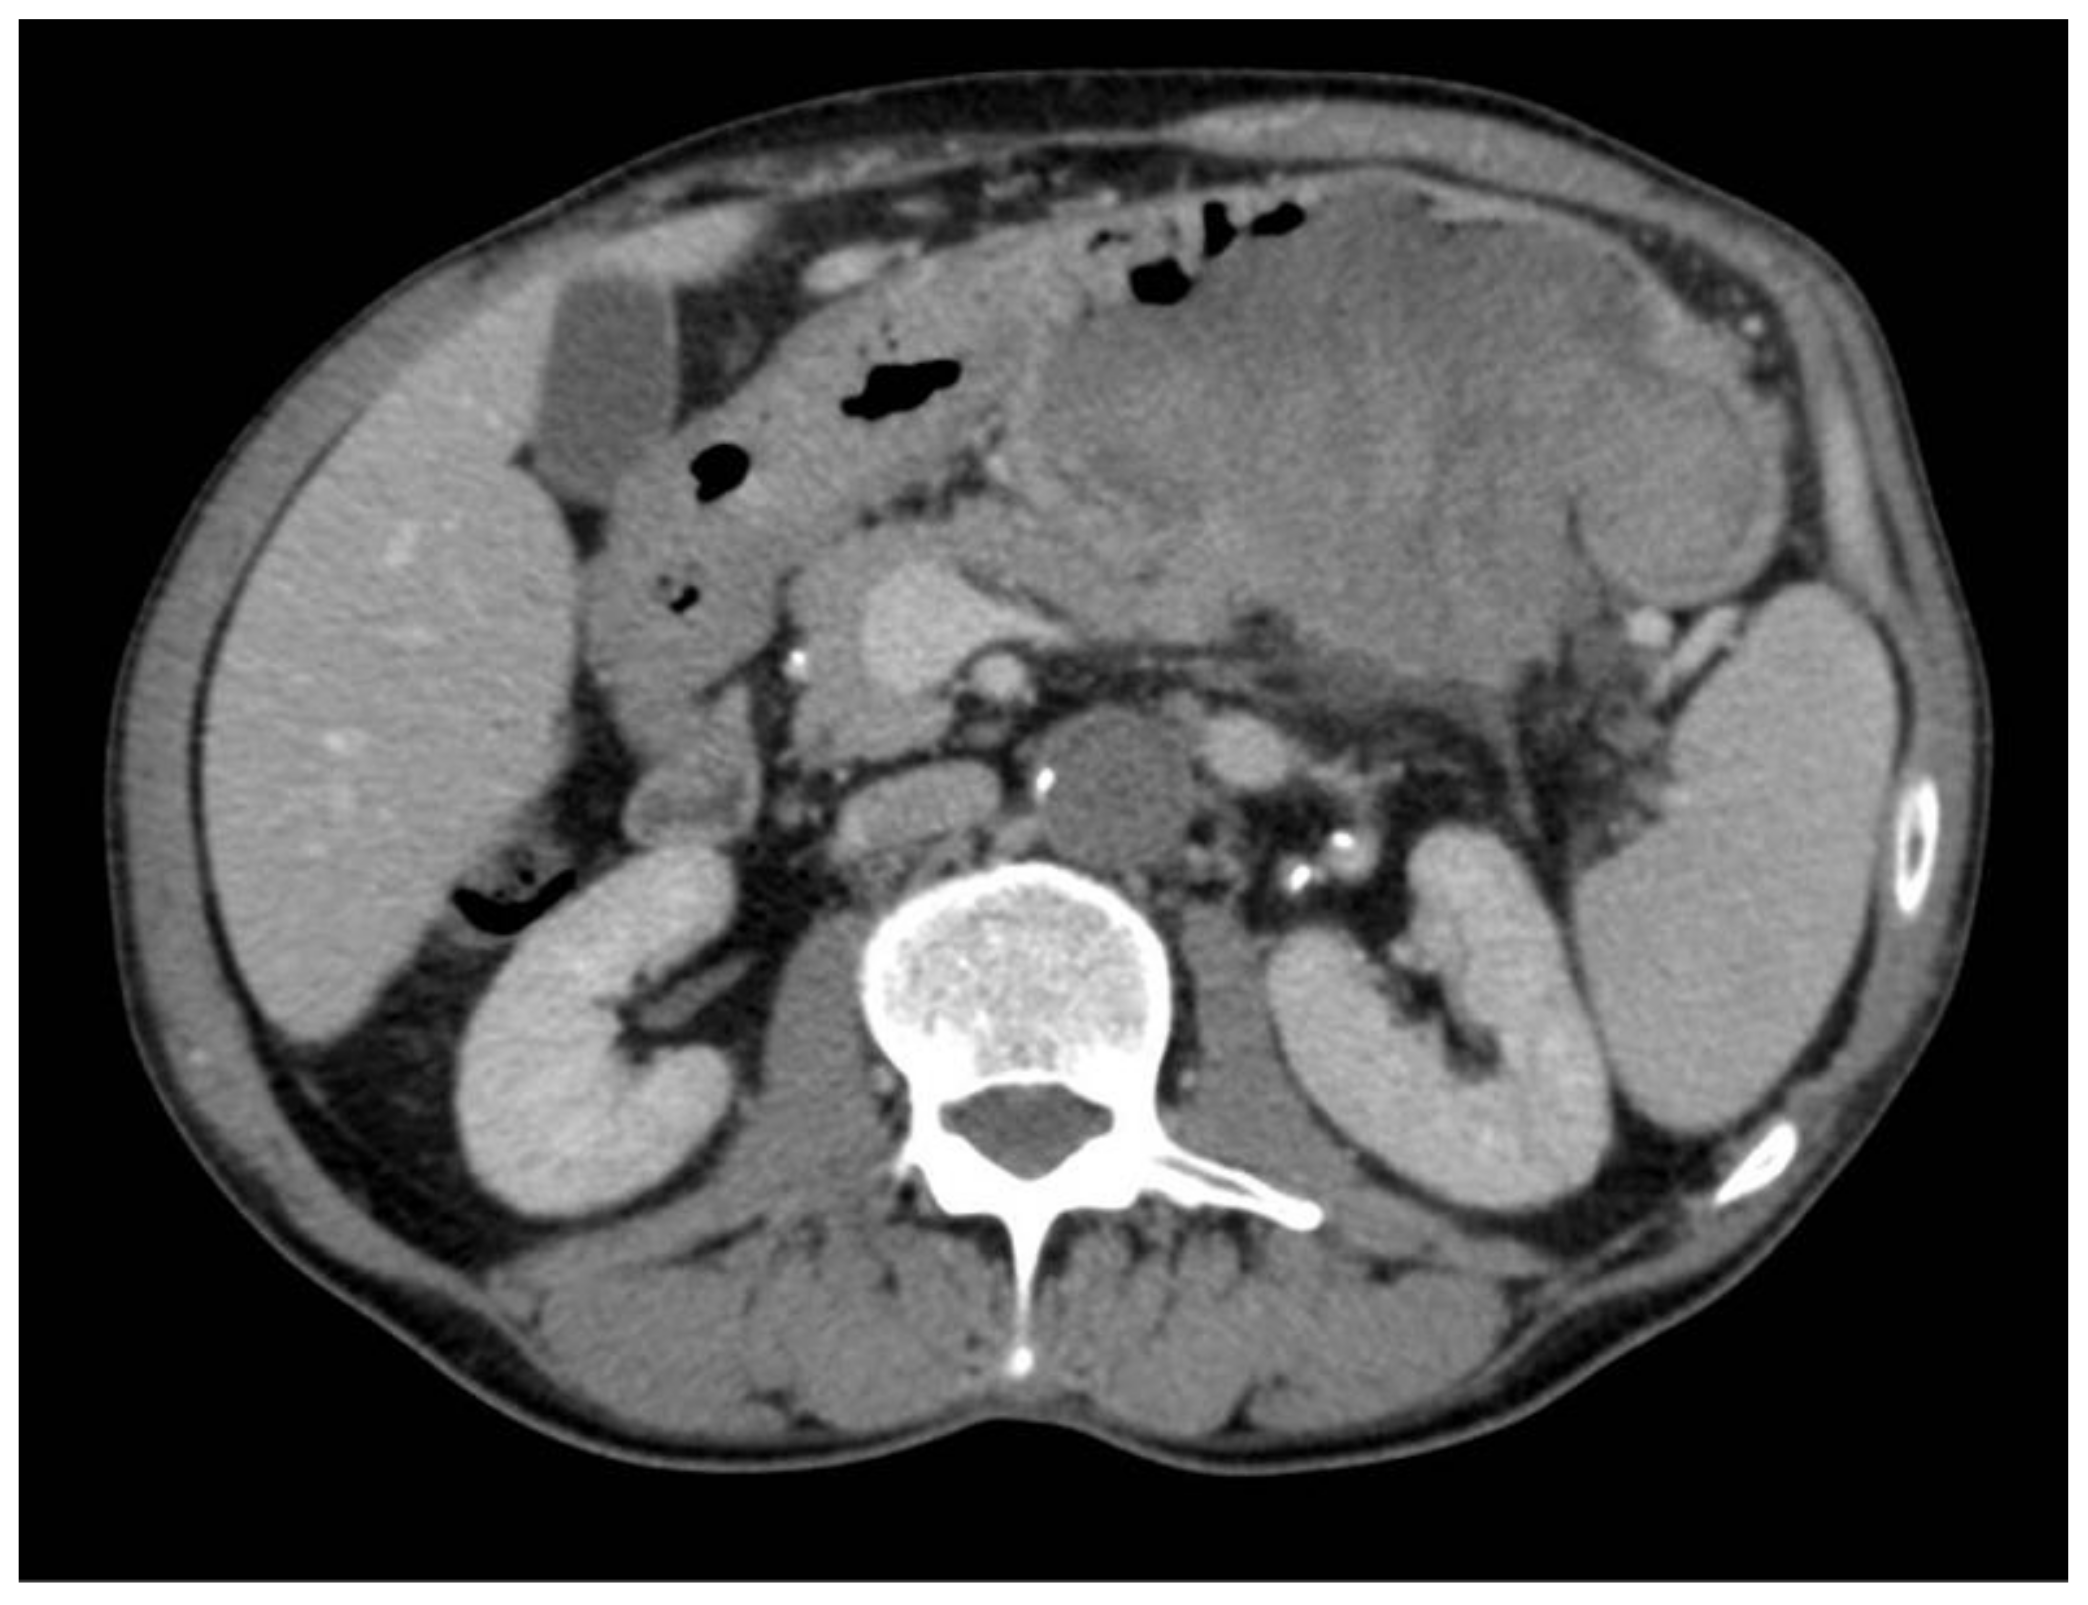

2. Case Report